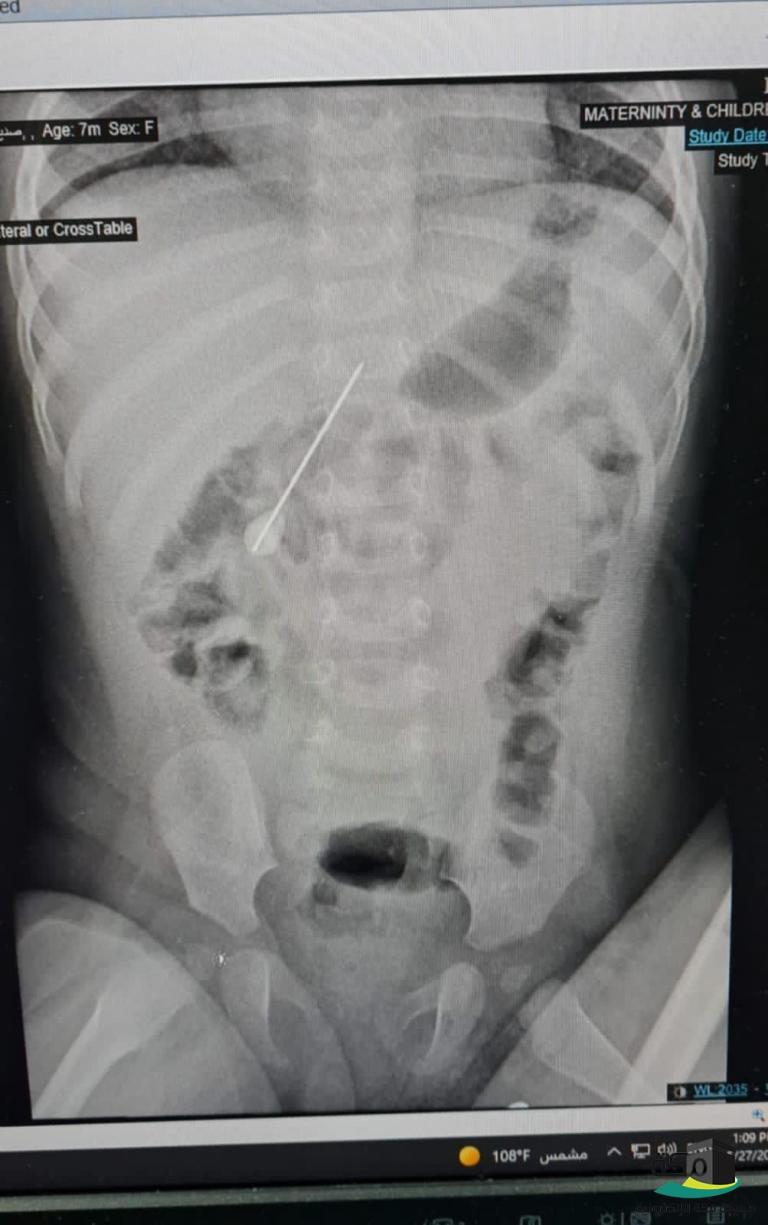

حيث وصلت الرضيعة لقسم الطوارئ بالمستشفى، وهي في حالة بكاء مفاجئ لايعلم ذويها ماهو سببه، وبعد معاينة الحالة وعمل الفحوصات اللازمة لها تبين وجود إبرة كبيرة الحجم يبلغ طولها 5 سم ونصف وأستقرت في الأمعاء.

وعلى الفور شُكل فريق طبي من أطباء جراحة الأطفال وقسم المناظير وقسم التخدير للتعامل مع الحالة وتجهيز الرضيعة لعمل المنظار دون تدخل جراحي حيث تم إخراج الإبرة بالمنظار رغم صعوبة ذلك لكون الطفلة مازالت رضيعة وكبر حجم الإبرة .

وتكللت العملية بالنجاح بفضل الله تعالى في وقت قياسي تم على إثرها ازالة الإبرة والتأكد من ألتئام الثقب الذي كان في الأمعاء بسبب إنغراس الإبرة والذي أدى إلى تسرب بسيط في الهواء وقد غادرت الرضيعة المستشفى وهي تتمتع بصحة جيدة – ولله الحمد.